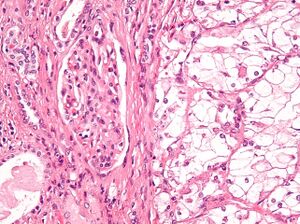

| Micrograph showing the most common type of kidney cancer (clear cell renal cell carcinoma). H&E stain. | |

The most common type of kidney malignancy is renal cell carcinoma,[11] which is thought to originate from cells in the proximal convoluted tubule of the nephron.[9][12] Another type of kidney cancer although less common, is transitional cell cancer (TCC) or urothelial carcinoma of the renal pelvis.[13] The renal pelvis is the part of the kidney that collects urine and drains it into a tube called the ureter.[13] The cells that line the renal pelvis are called transitional cells, and are also sometimes called urothelial cells. The transitional/urothelial cells in the renal pelvis are the same type of cells that line the ureter and bladder. For this reason TCC of the renal pelvis is distinct from RCC and is thought to behave more like bladder cancer.[13] Other rare types of kidney cancers that can arise from the urothelial cells of the renal pelvis are squamous cell carcinoma and adenocarcinoma.[9]

Renal cell carcinoma has been further divided into sub-types based on histological features and genetic abnormalities. The 2004 WHO Classification of the Renal Tumors of the Adults describes these categories:[17]

- Clear cell RCC